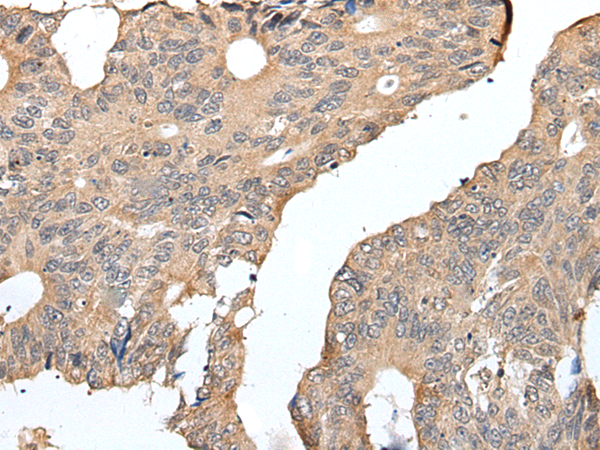

IHC positive control: |

Human colorectal cancer |

IHC Recommend dilution: |

25-100 |